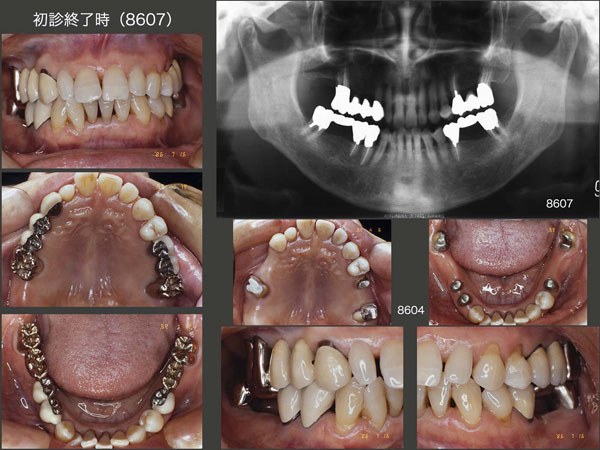

初診は1985年2月,49歳女性.東京歯科大学千葉病院勤務の時の患者さんであり,私は歯科医師になって5年目.全顎にわたり不適合な補綴装置が装着されており,歯周病も進行していた.歯周基本治療,歯周外科処置を施したのちに固定式のブリッジを製作した.

1986年7月,初診から1年5ヵ月後の治療終了時の状態.(スライド中段は,86年4月,ブリッジ装着前の支台歯の状態.)当時の自分は,これが精一杯の治療で,可撤式のブリッジ(コーヌス義歯)は考えていなかった.また,当時歯内療法は保存科で行って貰ったが,ここまで抜髄する必要があったのか疑問である.もう少し,有髄歯に拘って貰いたいと思うが,当時私を含めて,そこまでの考えには及んでいなかった.